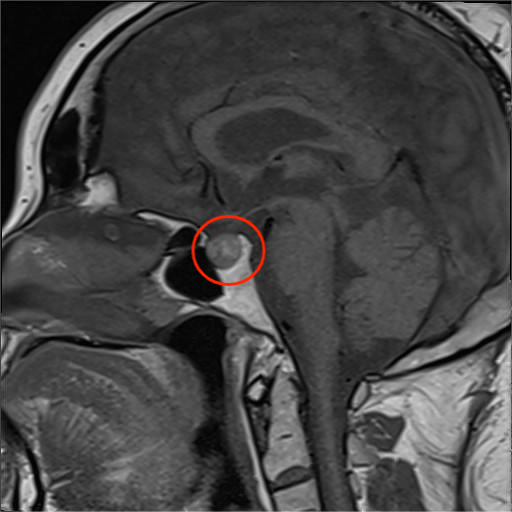

入院后,经完善相关检查,提示钟女士皮质醇升高并节律消失,头颅MRI检查提示垂体右份存在1cm结节,考虑垂体瘤。

钟女士头颅MRI检查图像